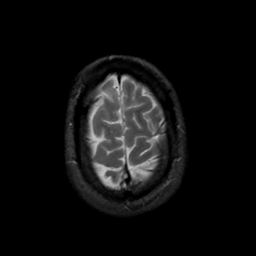

MR Study #17, July 7, 1991 -- Slice #44

[Home][Help][Clinical][Tour 1][Tour 2] Slice 44